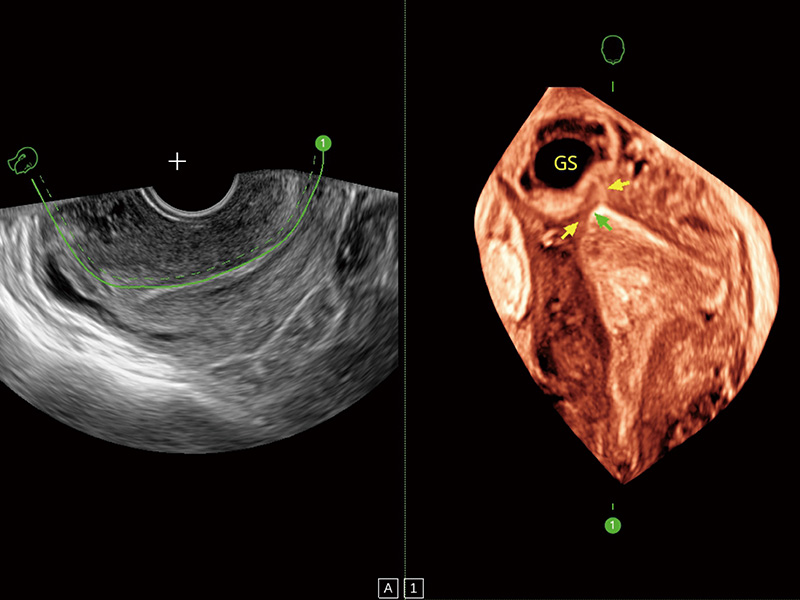

临床图

中央型宫腔粘连

单角子宫

子宫内膜息肉

输卵管间质部妊娠

腔内三维成像技术获得显著提升,超大扇角在满足日常基础扫查的同时,支持卵泡自动测量及多种三维渲染模式,为您提供更多的诊断信息,尤其是在子宫畸形的诊断,内膜及肿瘤占位观测中起到了重要的作用。